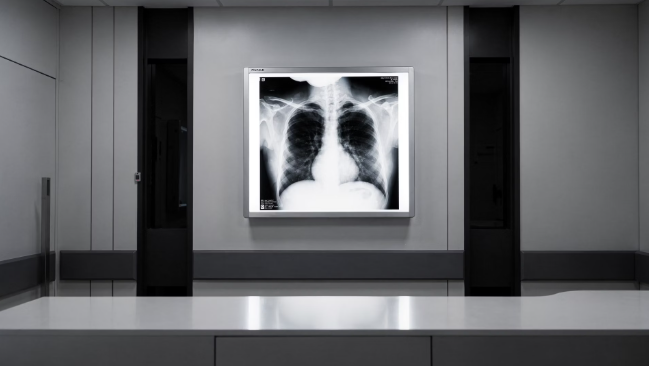

- 흉부 X-선 검사(기본): 가장 빠르고 간편하게 폐의 이상 유무를 파악하는 1차 선별 방법입니다.

- 1차 선별의 핵심: 폐 상부에 하얀 그림자나 공동(구멍)이 발견되면 결핵을 강력히 의심할 수 있습니다.

- 간접 촬영 vs 직접 촬영: 최근에는 고해상도 디지털 직접 촬영을 통해 미세한 병변까지 잡아내어 오진율을 낮추고 있습니다.

- 한계점 인지: X-선만으로는 과거에 앓았던 결핵 흔적인지, 현재 활동성 결핵인지 100% 구분하기 어려울 수 있어 추가 검사가 필요합니다.

흉부 X-선 검사는 결핵 진단의 '입문'과 같습니다. 하지만 폐렴이나 폐암과 영상 소견이 유사할 수 있다는 점을 명심해야 합니다. 2026년 대한결핵협회 자료에 따르면, 65세 이상 노인 인구의 경우 무증상 상태에서 X-선 검사만으로 결핵을 조기 발견하는 비율이 약 35%에 달합니다.

이는 어르신들이 매년 1회 무료 결핵 검진을 받아야 하는 가장 큰 이유이기도 합니다. 영상 의학 전문의의 판독 결과 '활동성 결핵 의심' 소견이 나온다면, 즉시 전염성 여부를 확인하기 위한 객담 검사 단계로 넘어가야 합니다.